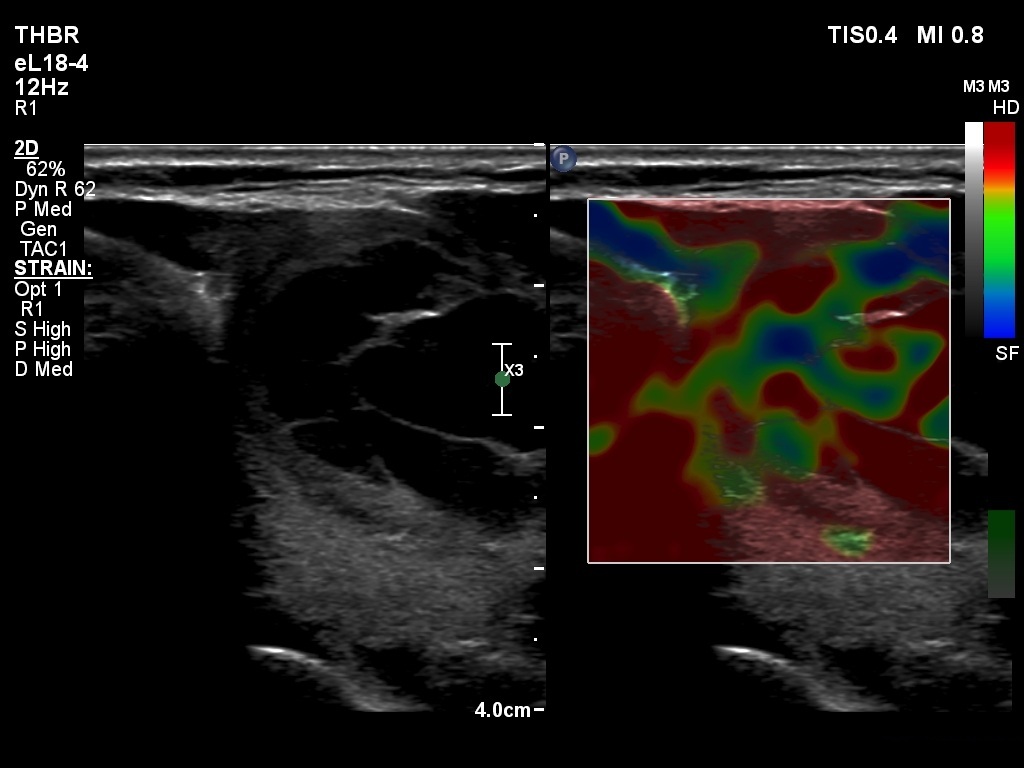

Ultrasonography. The thyroid was echonormal. The right lobe contained several discrete areas without any clinical significance. There was multi-chambered cystic nodule in the left lobe. The nodule had echonormal solid part and presented halo sign.

- The distinction between a multi-chambered cyst and a spongiform cyst is important, because in the latter the risk of malignancy is practically zero. In spongiform cysts almost the entire nodule is composed of cystic areas, and there is very small proportion of solid areas.

- The cyst has just started refilling after the evacuation.